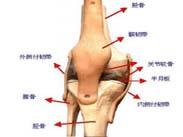

• 半月板損傷

半月板損傷(meniscus injury)是膝部最常見的損傷之一,多見于青壯年,男性多于女性。國外報道內、外側半月板損傷之比為4~5∶1,而國內報道相反,其比例為1∶2.5。...